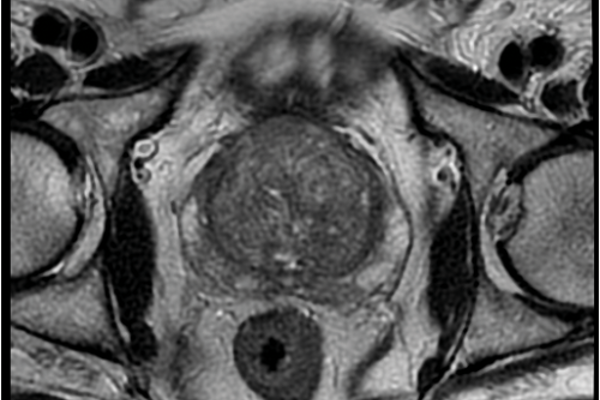

Meeting in the middle: a review of the rendezvous technique to treat impassable ureteric strictures and transected ureters